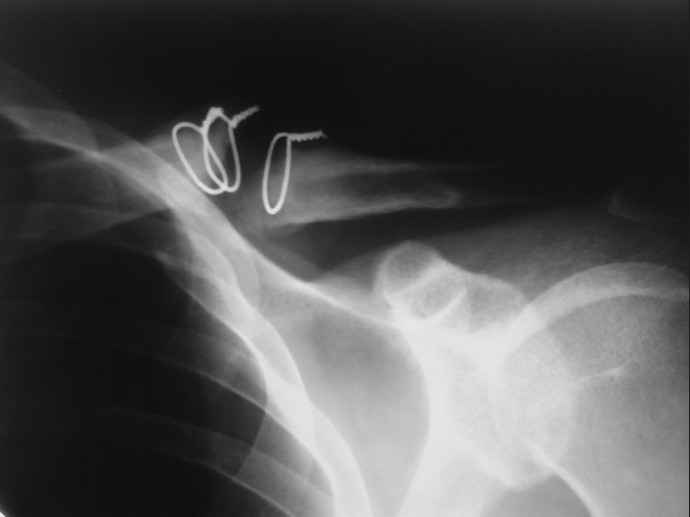

[Ortho] Ложный сустав ключицы

34 года, около года назад,оперирован в одном из городских ЛПУ области.Через 2 мес. удалён (стержень Богданова?Спица ?).Активно занимался спортом,в последнее время около месяца (со слов стало беспокоить патолог.подвижность и хруст). На снимках ложный сустав...

R-гр в приложении